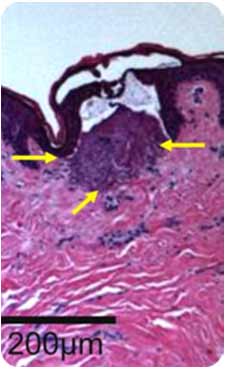

The PERMEA 1927 nm hand piece is very unique and yet similar to Clear and Brilliant, similar in that it creates micro-channels in the skin. The PERMEA hand-piece creates micro channels that are wider and shallower which increase the permeability of the skin 17 times! This means it allows products to go 17 times deeper, more penetration of skin solutions when adding product after treatment.

What does this really mean? The best analogy of the PERMEA LASER treatment is the skin is being aerated with micro channels that have a V shape channel similar to a slice of pizza. Now visualize the wider, shallow aeration without a lot of heat. This process allows permeability of product put on the skin right after the procedure and with these wider channels your skin will soak up your topical Vitamin C or Growth Factor. This synergistic relationship of procedure and products is key to optimum rejuvenation.